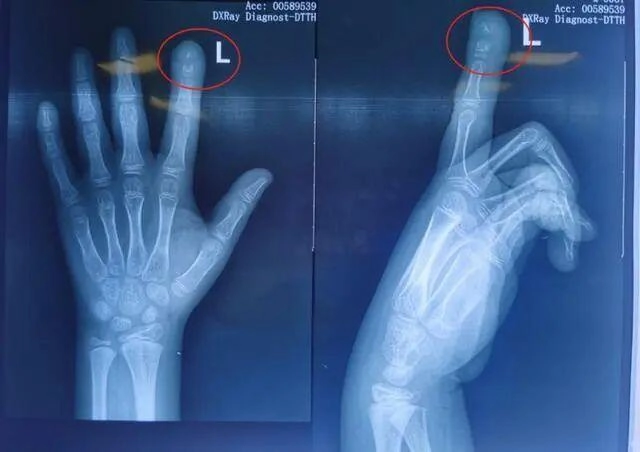

Khi cô Li đưa con trai đến bệnh viện lần nữa, phim chụp X-quang cho thấy tình trạng nhiễm trùng đã ảnh hưởng đến đốt ngón tay - có một vùng xương bị phá hủy lớn. Cô Li lo lắng nên nhanh chóng đưa con đến Khoa Chỉnh hình của Bệnh viện Nhi Hồ Nam để tiếp tục điều trị.

Lúc này, Tiểu Quy được chẩn đoán mắc bệnh viêm tủy xương ngón trỏ trái. Bác sĩ trưởng khoa chỉnh hình Bệnh viện nhi Hồ Nam kết luận, Tiểu Quy sẽ được điều trị chống nhiễm trùng, sau khi kiểm soát được tình trạng nhiễm trùng thì sẽ tiến hành điều trị gãy xương bệnh lý ở giai đoạn 2 và lấp đầy khuyết xương.